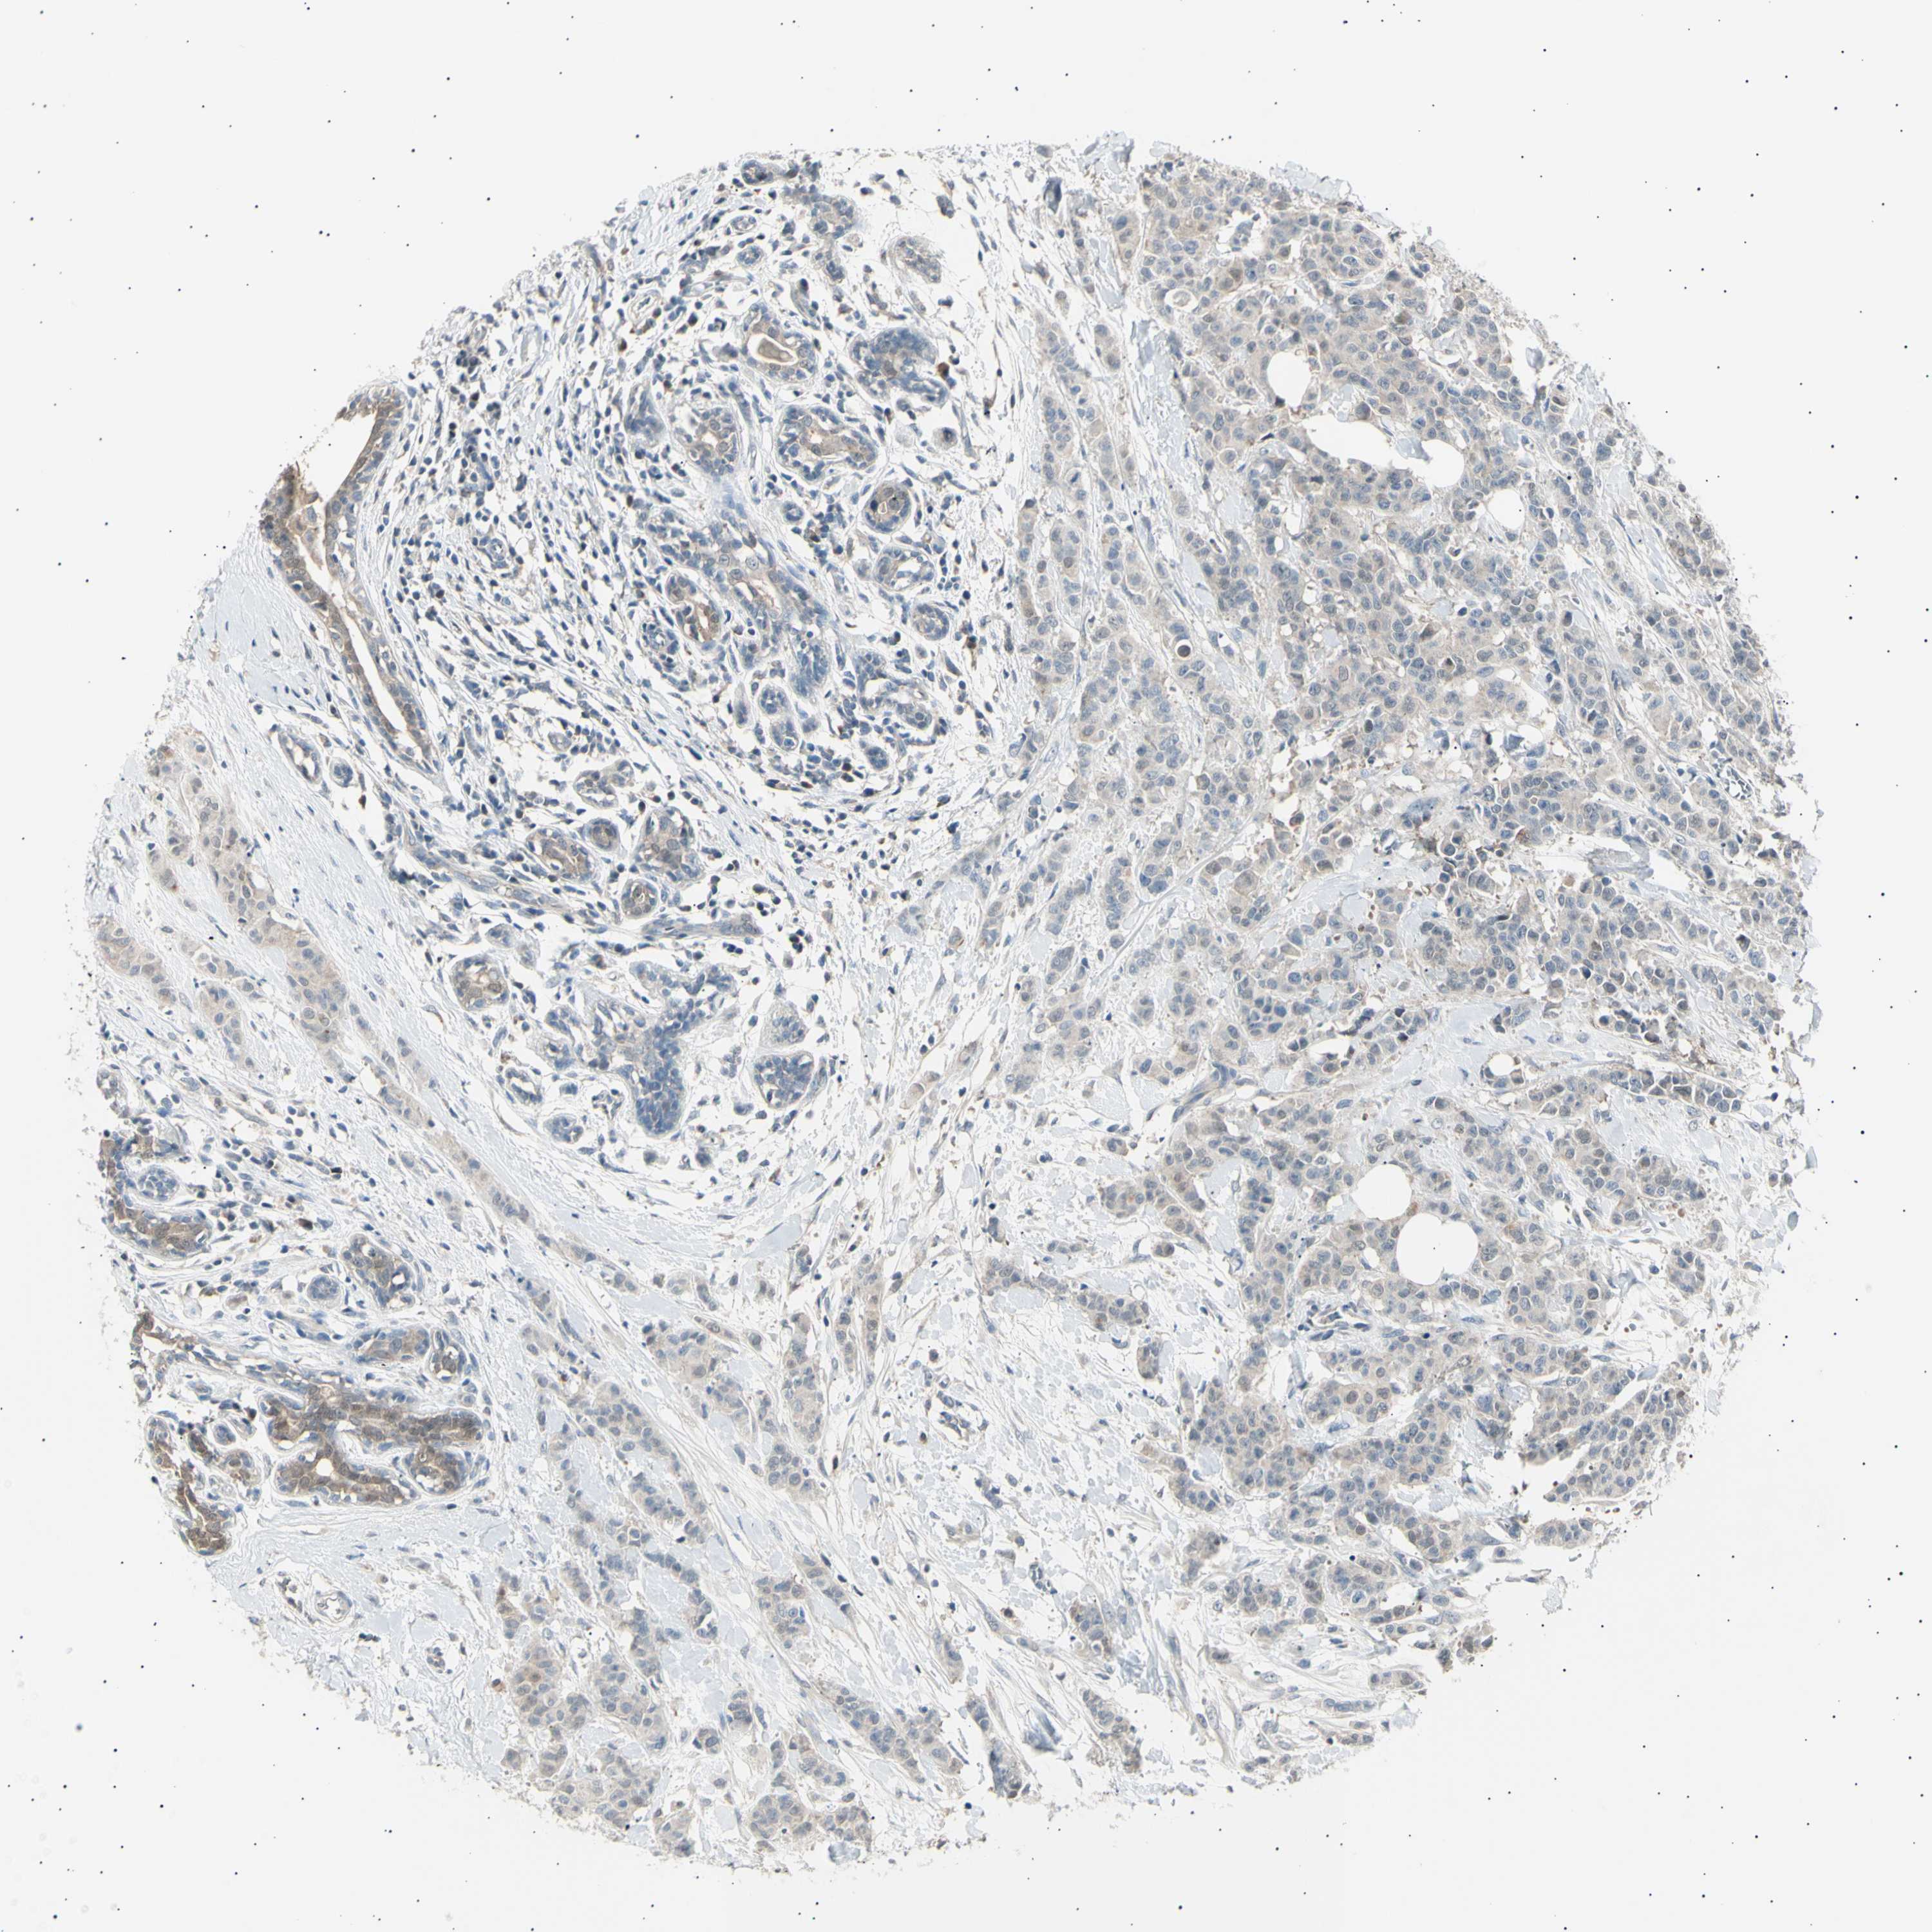

CANCER BREAST CANCER Show tissue menu

BRCA TCGA BRCA VALIDATION PROTEIN EXPRESSION